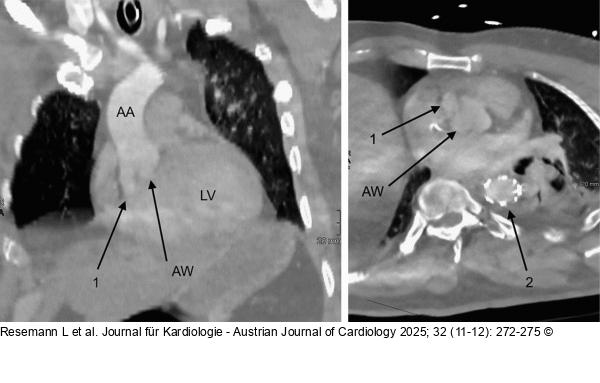

Abbildung 3: Aorten-CT Postinterventionelles Kontroll-CTA nach TEVAR: AA – Aorta ascendens; LV – linker Ventrikel; AW – Aortenwurzel; 1 – Pseudoaneurysma im Bereich des nonkoronaren bzw. rechtskoronaren Sinus; 2 – expandierter Stentgraft in der proximalen Aorta descendens |

Postinterventionelles Kontroll-CTA nach TEVAR: AA – Aorta ascendens; LV – linker Ventrikel; AW – Aortenwurzel; 1 – Pseudoaneurysma im Bereich des nonkoronaren bzw. rechtskoronaren Sinus; 2 – expandierter Stentgraft in der proximalen Aorta descendens |